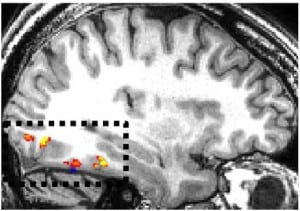

Fusiform_Gyrus_clusters

Previous article: Treating Seizures Leads to Face Blindness Discovery: Q&A with Josef Parvizi